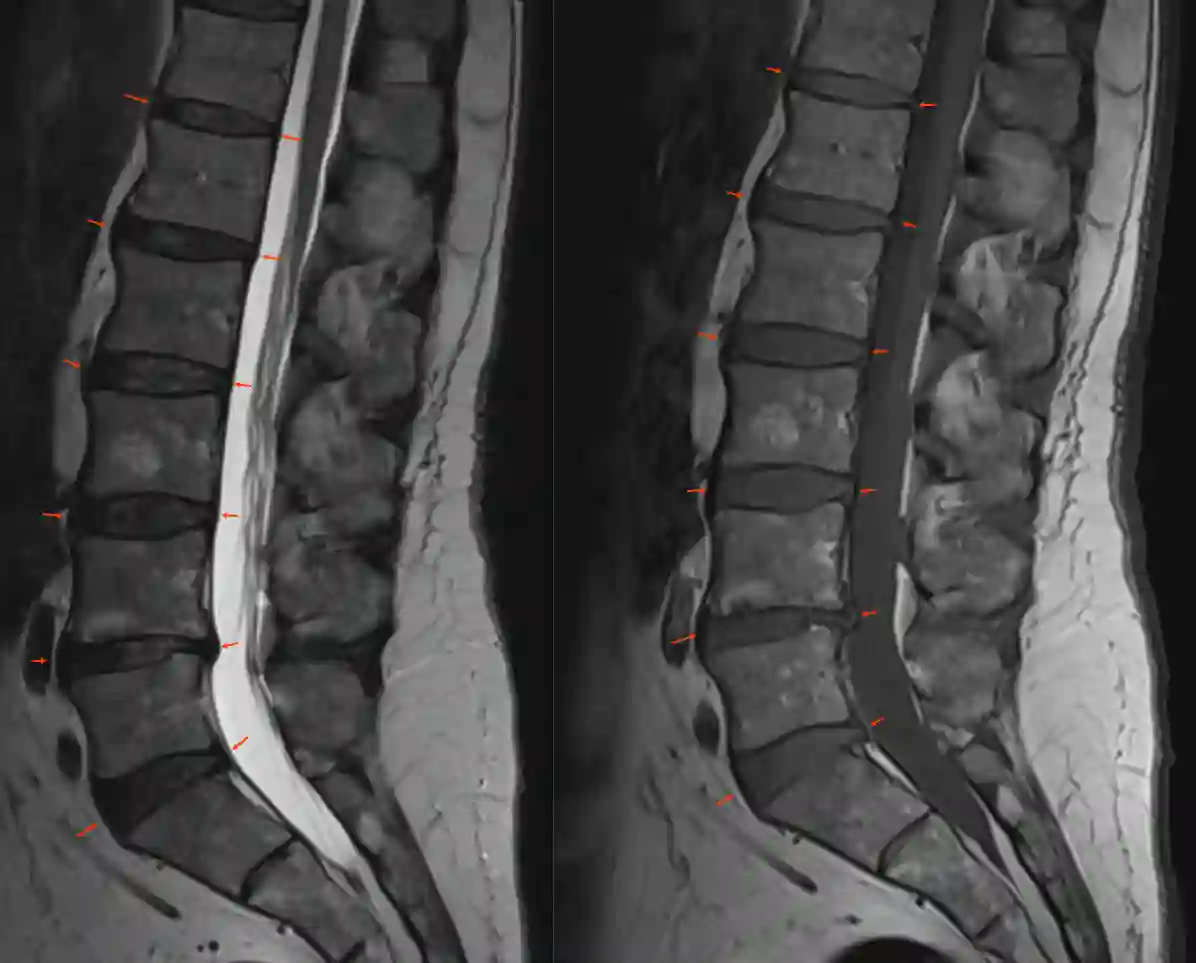

Riss im Anulus Fibrosus der Bandscheibe

Medianer Riss im Anulus fibrosus einer lumbalen Bandscheibe im axialen MRT in einer T2 Sequenz.s